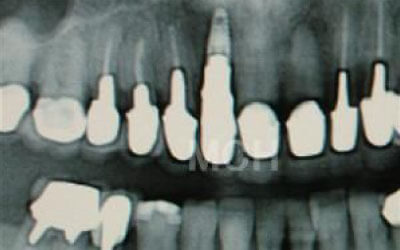

しばらくすると、抜けたままでも慣れてしまうことがありますが、その後に大きな問題が生じることがあります。

1 周囲の歯が早く抜ける

抜けた歯にかかるはずだった噛む力が、知らず知らずのうちに他の歯に負担をかけてしまいます。その結果、残っている歯が突然折れてしまい、抜歯が必要になることがよくあります。

2 歯が傾いてくる、落ちてくる

歯は互いに支え合い、バランスを保っています。そのため、歯が抜けると支えがなくなり、抜けた部分の両隣の歯が傾いたり、上の歯が下に移動してきたりすることがあります。